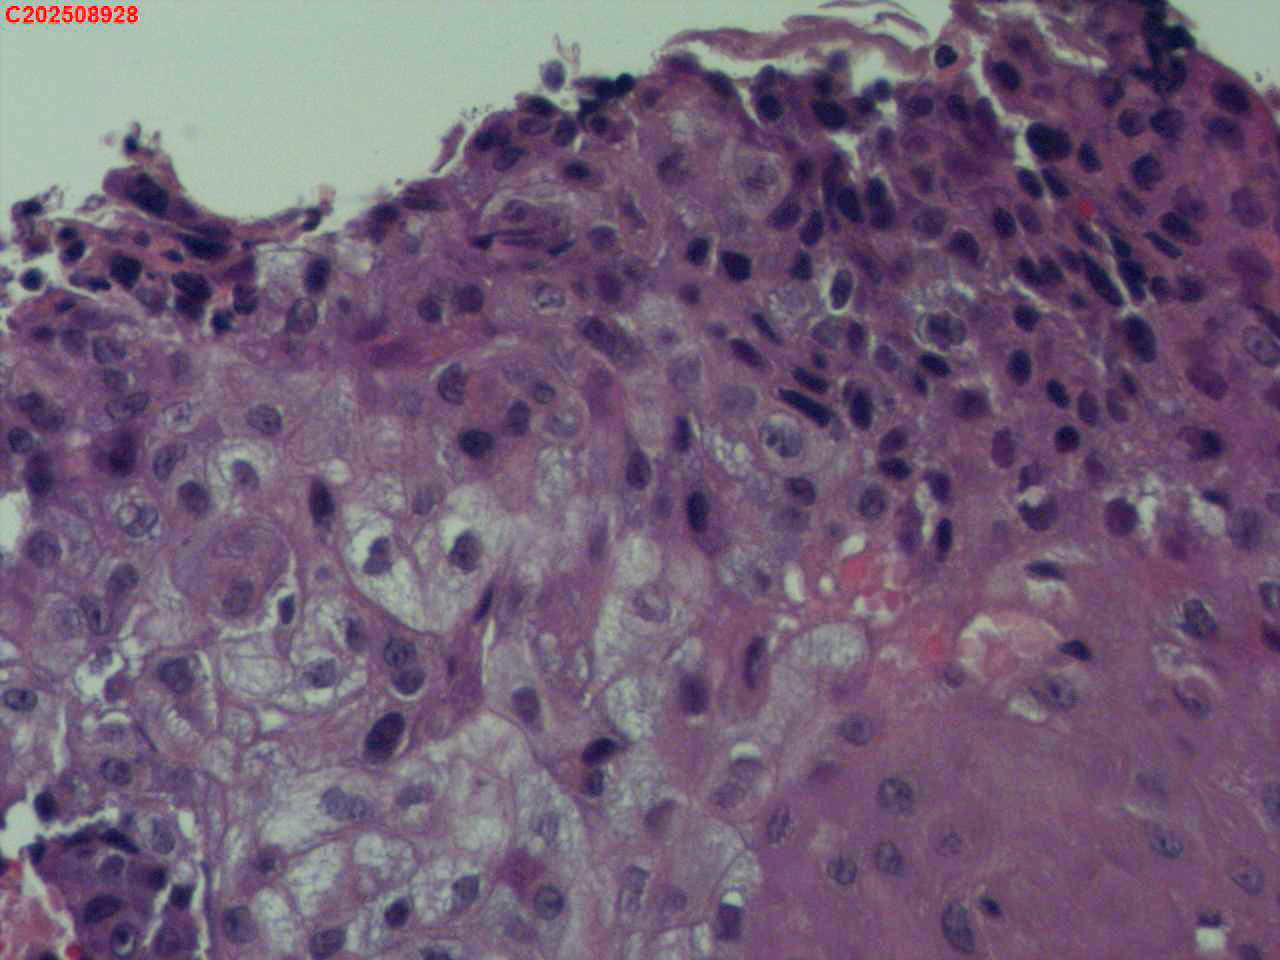

喉部右侧、声带下方咬检

喉室内右侧声带下方新生物。

考虑鳞癌

鳞癌,有微浸润